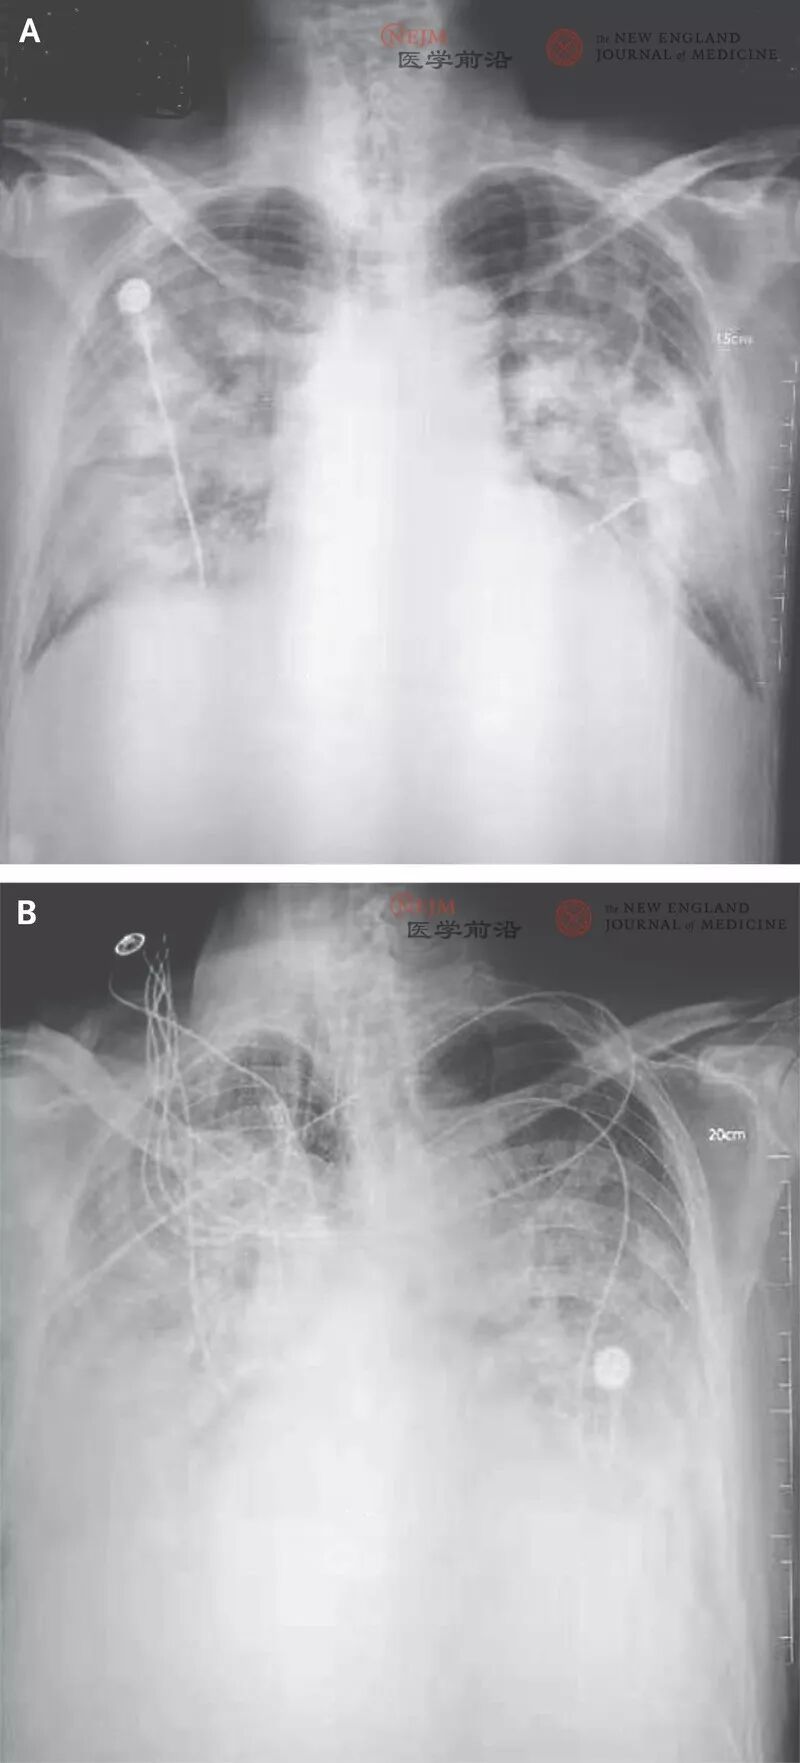

在临床症状出现后4天,咳嗽和肺部不适症状加重,但发热症状缓解,基于CT扫描的结果做了肺炎诊断。此患者的职业为海鲜市场的零售商贩。患者2初始症状从2019年12月20日开始,出现了发热和咳嗽。在起病后7天出现呼吸困难且后续2天进行性加重(胸片资料见图1),在此期间进行了机械通气。该患者曾经常出入海鲜市场采购。患者1和患者3在经过治疗后于2020年1月16日出院,但患者2在2020年1月9日死亡,没有采集到患者的组织标本。

图1. 胸片